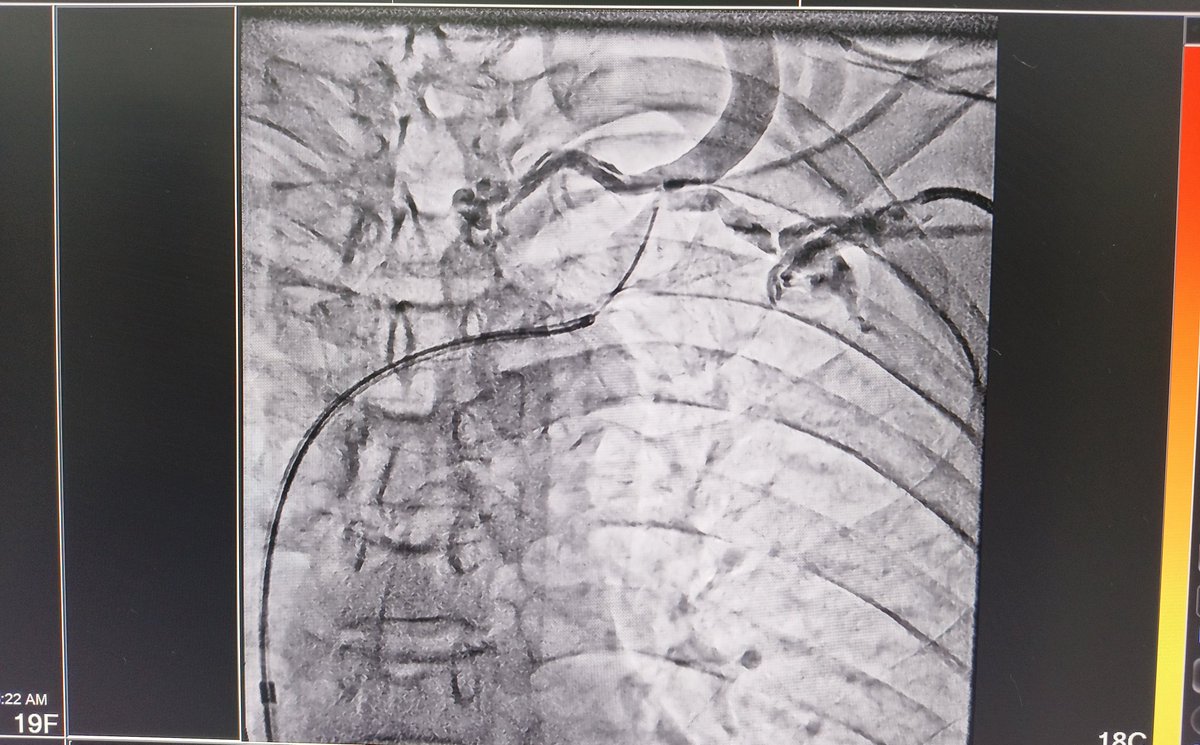

60/f

right IJV HD cath & TCC 1 yr back

Left elbow AVF primary failure

Now created right BV AVF

Soon got Right UL edema

VenoGm - stenosis at innominate

Plasty done > adequate flow> edema gone > discharge > AVF can be used now 😊

#interventionnephrology #nephrologistincathlab